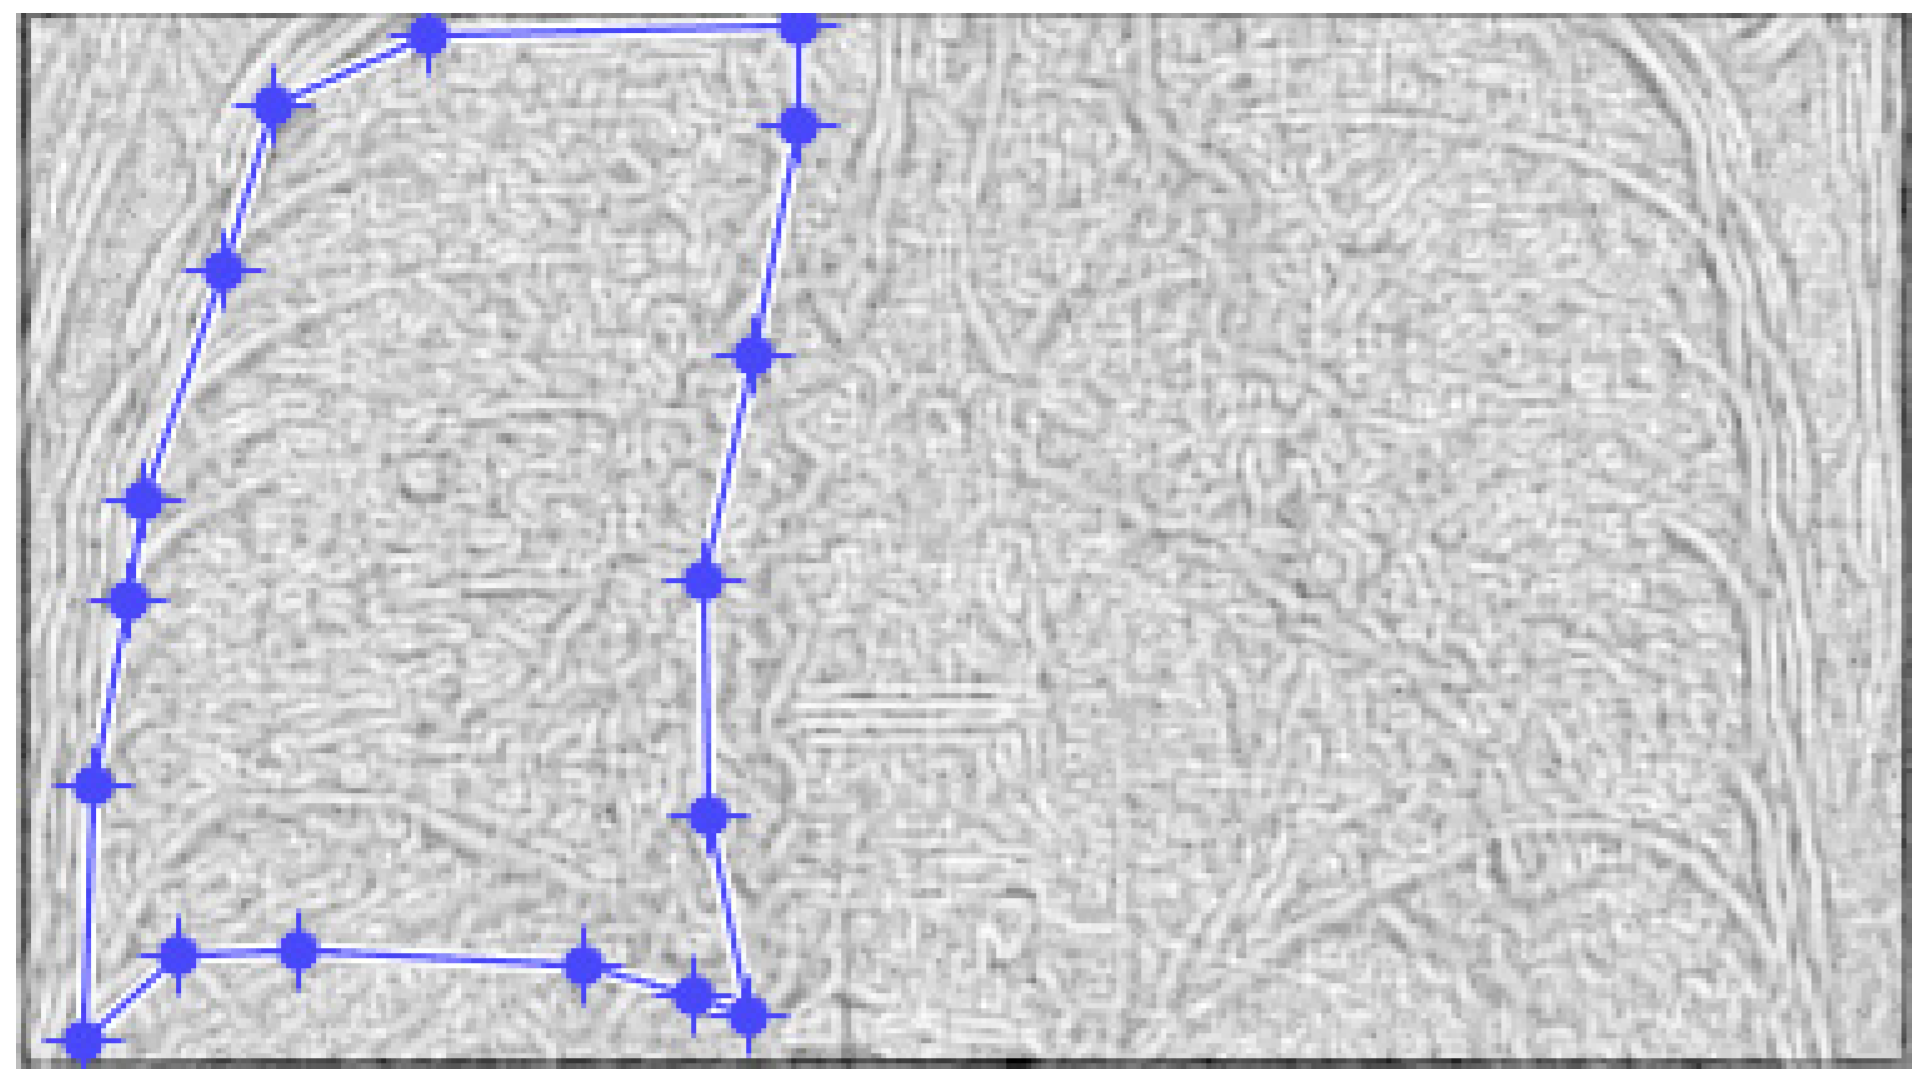

Figure 4 and Figure 5 present the defined masks for the left lung and right lung, framed in blue borders.

Figure 4. Defining the mask for the left lung of the first patient.

Fractalfract 07 00285 g004

Figure 5. Defining the mask for the right lung of the first patient.

Fractalfract 07 00285 g005